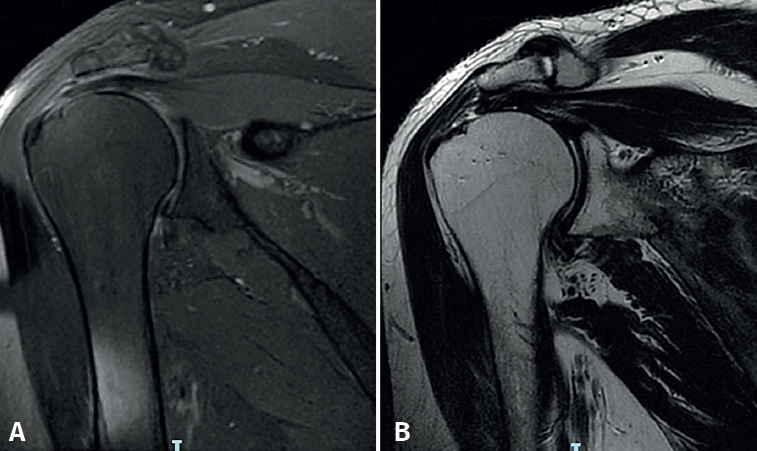

Compression phase in the second row (Figure 2B)

In this phase, the four sutures (8 strands) corresponding to the anchors of the first or medial row are knotted. For this purpose, the sutures of the posterior anchor will have been retrieved through the PSL portal and those of the anterior anchor through the ASL portal. The type of knot used at this stage is the slip knot (in our practice, the giant type), followed by three half safety knots. Only one of every two remaining strands is cut. In this way, an adaptation of the end of the tendon to the entire footprint will have been achieved.